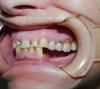

kirovsasa Опубликовано 31 января, 2010 Автор Поделиться Опубликовано 31 января, 2010 Если говорить о этой работе, то движения в одном суставе были очень ограничены, и челюсть закрывалась рывками и со смещением. Это было 2 года назад и более подробно я наверное уже не вспомню. А работу привёл в пример(еле фотки нашёл, все папки перерыл). Чтобы Вы не думали,что я студент. Ссылка на комментарий

kirovsasa Опубликовано 31 января, 2010 Автор Поделиться Опубликовано 31 января, 2010 По поводу , если объединять, то как(можно цифрами пожалуйсто)? А наличие встечных коронок на имплантатах (жевательная группа слева) как может повлиять на это? Я такие углы один раз в жизни видел и я(когда делали эту работу) звонил "знающему человеку" и мне дали ответ- что при серьёзных проблемах в суставах, такое может быть .Знаний на то, чтобы правильно диагностировать и лечить такую паталогию у меня нет и на консилиуме в клинике было принято решение -оставить суставы как они есть. На здаче работы контакты на коронках были аналогичные . как на зубах до препарирования. Есль бу это были ошибочные настройки - наверное бы так не получилось? Примерно , что помню из клинической ситуации ,я уже у этого пациента описывал. А вообще я вдруг для себя понял, что снимков обычных работ у меня нет (всё с странностями). Ссылка на комментарий

kirovsasa Опубликовано 1 февраля, 2010 Автор Поделиться Опубликовано 1 февраля, 2010 (изменено) По поводу углов , Вы правда думаете, что с такими жевых людей нет. Я сам при гипсовке и настройке диагностических моделей присутствовал(с теми зубами и суставами пациент жил до 40 лет без протезирований и лечений). Поэтому такиеже показатели и оставили для настоек для работы. Я конечно понимаю, что поступил не правильно- надо было отправить на лечение суставов к специалистам,а потом протезировать, но получилось так . Изменено 1 февраля, 2010 пользователем kirovsasa Ссылка на комментарий